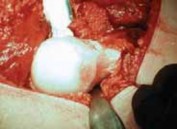

E F

TECH FIG 3 • A. The trochanteric fragment is mobilized anteriorly. The joint capsule is prepared. The insertion of the piriformis tendon onto the trochanter is intact. B. Schematic of the capsulotomy. C. By flexion and external rotation, the leg is placed in the anterior side bag. This maneuver allows anterior dislocation of the hip. D. Overview across the acetabulum after dislocation of the hip. E. Dislocated femoral head. For better visualization, two blunt Hohmann retractors are placed around the femoral neck. The anterior asphericity and the fibrillated cartilage in the area of impingement are visible. F. Intraoperative view of a left acetabulum. A labral ganglion extending into the soft tissues is visible at the anterosuperior acetabular rim, and the anterosuperior acetabular cartilage flap is seen. come posteriorly, creating enough space to visualize the entire acetabulum.

1. Now, a full view of the acetabulum is obtained (

TECH

### FIG 3F). INTRA-ARTICULAR SURGERY FOR FEMOROACETABULAR IMPINGEMENT Site Assessment 2. Before the hip is dislocated, the presence and amount of effusion and synovitis are noted.

1. The head–neck junction is observed for the presence of a nonspherical extension (

TECH FIG 4

).

32. The femoral head is dislocated anteriorly, making it possible to fully evaluate the femoral head–neck junction as well as the acetabulum.

TECHNIQUES TECH FIG 4 • Inspection of the femoral head in situ. The anterior asphericity can be seen. Dynamic inspection with flexion and internal rotation shows the area of impingement. 1. Acetabular version is assessed and compared with the preoperative radiographs.

2. With a blunt probe, the integrity of the labrum and the articular cartilage is determined, and the quality and quantity of any damage or injury is documented.